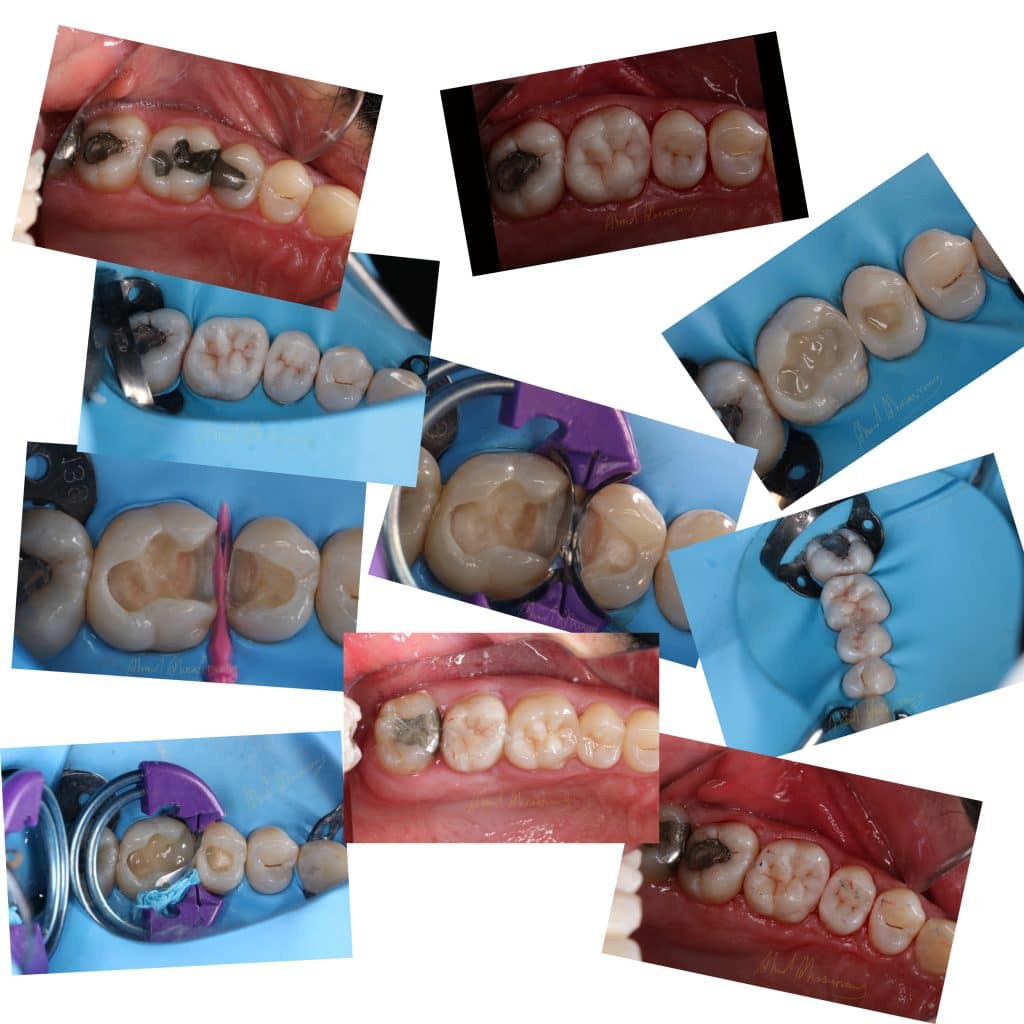

Patient complaining from bad contact and pain during cold 🥶 lasting for few second

decision made to remove old amalgam restoration .

steps:

remove old restoration

cavity design

immediate dentin sealing(IDS)

Bioclear matrix system

sixth generation se bond

finishing and polishing (enhance kit from dentsply)